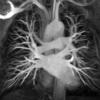

vessesls MR

Date: 02/25/2013

Views: 3220